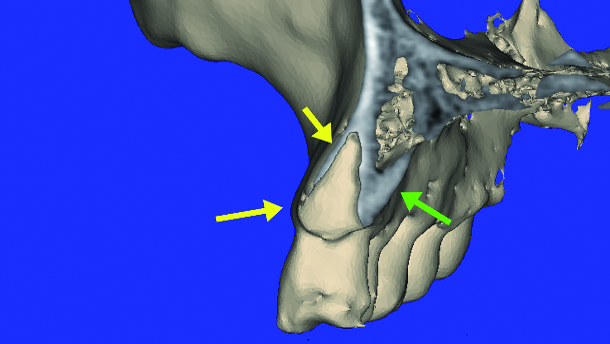

The use of interactive treatment planning software adds advanced software tools to help remove scatter, improve the diagnostic capabilities, while creating three dimensional reconstructed volumes that can be seen in all planes of view. The ability to navigate and ‘slice through’ 3-D volumes, known as ‘clipping’, provides unprecedented visualisation of the maxillo- mandibular structures. A maxillary 3-D volume ‘clipped’ through the right canine (marked in red) is seen in Figs. 4a and b. The 3-D reconstructed volume helps to further define the maxillary alveolar anatomy, tooth, and root position within the bone. An advanced software feature allows for manipulation of the grayscale density of the scan data (thresholding). This tool known as ‘segmentation’ can be used to reduce scatter from metal artifacts, such as crowns or fillings, and to separate one object from another. Through software segmentation, the maxillary right canine can be virtually extracted from the alveolus, illustrating the socket anatomy, the thin facial cortical plate (yellow arrows), and the palatal bone thickness (green arrow) (Fig. 5). The software allows the images to be enlarged for closer inspection (Fig. 6). Note the areas of good density and where the density is poor within the alveolus, superior to the root socket.

The capability to virtually remove a tooth and root from the bone can aid clinicians in making educated decisions regarding immediate extraction-to-implant placement, immediate-to-transitional restoration, and an appreciation of the potential ‘gap distance’, which may be present after implant placement. A simulated implant of the appropriate diameter and length can be positioned within the virtual socket to gain initial stabilisation as related to the desired restorative outcome (Fig. 7). The thin facial cortical bone can be clearly seen (yellow arrow), as can the thicker palatal bone (green arrow). The facial ‘gap’ between the implant and the facial cortical plate can be fully appreciated, and decisions made whether or not to fill the gap with bone (red arrows).